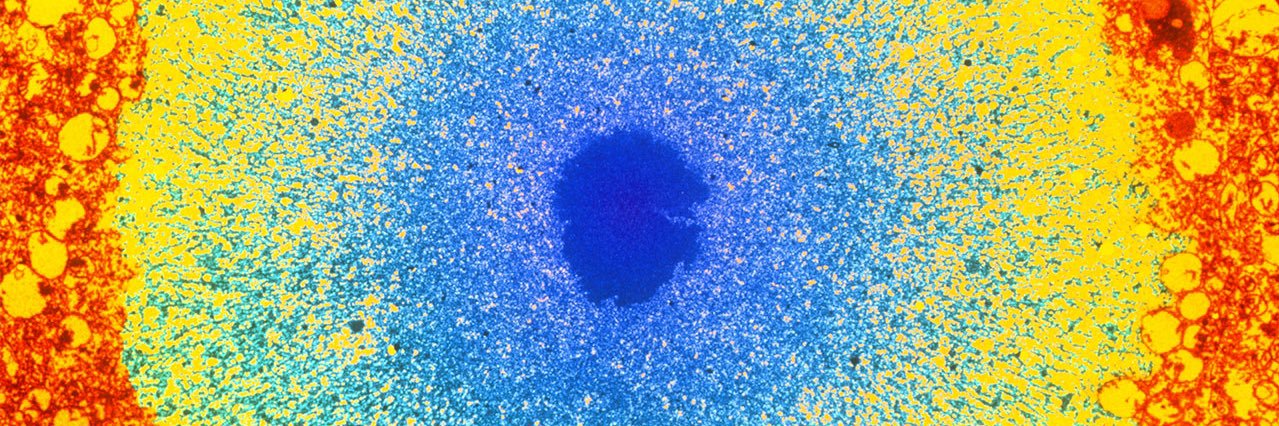

Finally published on Cell Death&Disease (@Nature group)! A comprehensive review I had the pleasure and the honor to write with prof. Paolo Calabresi (Università Cattolica del Sacro Cuore) and prof. @lvolpic (UAB).

🧠📚 #Neurology #Parkinson